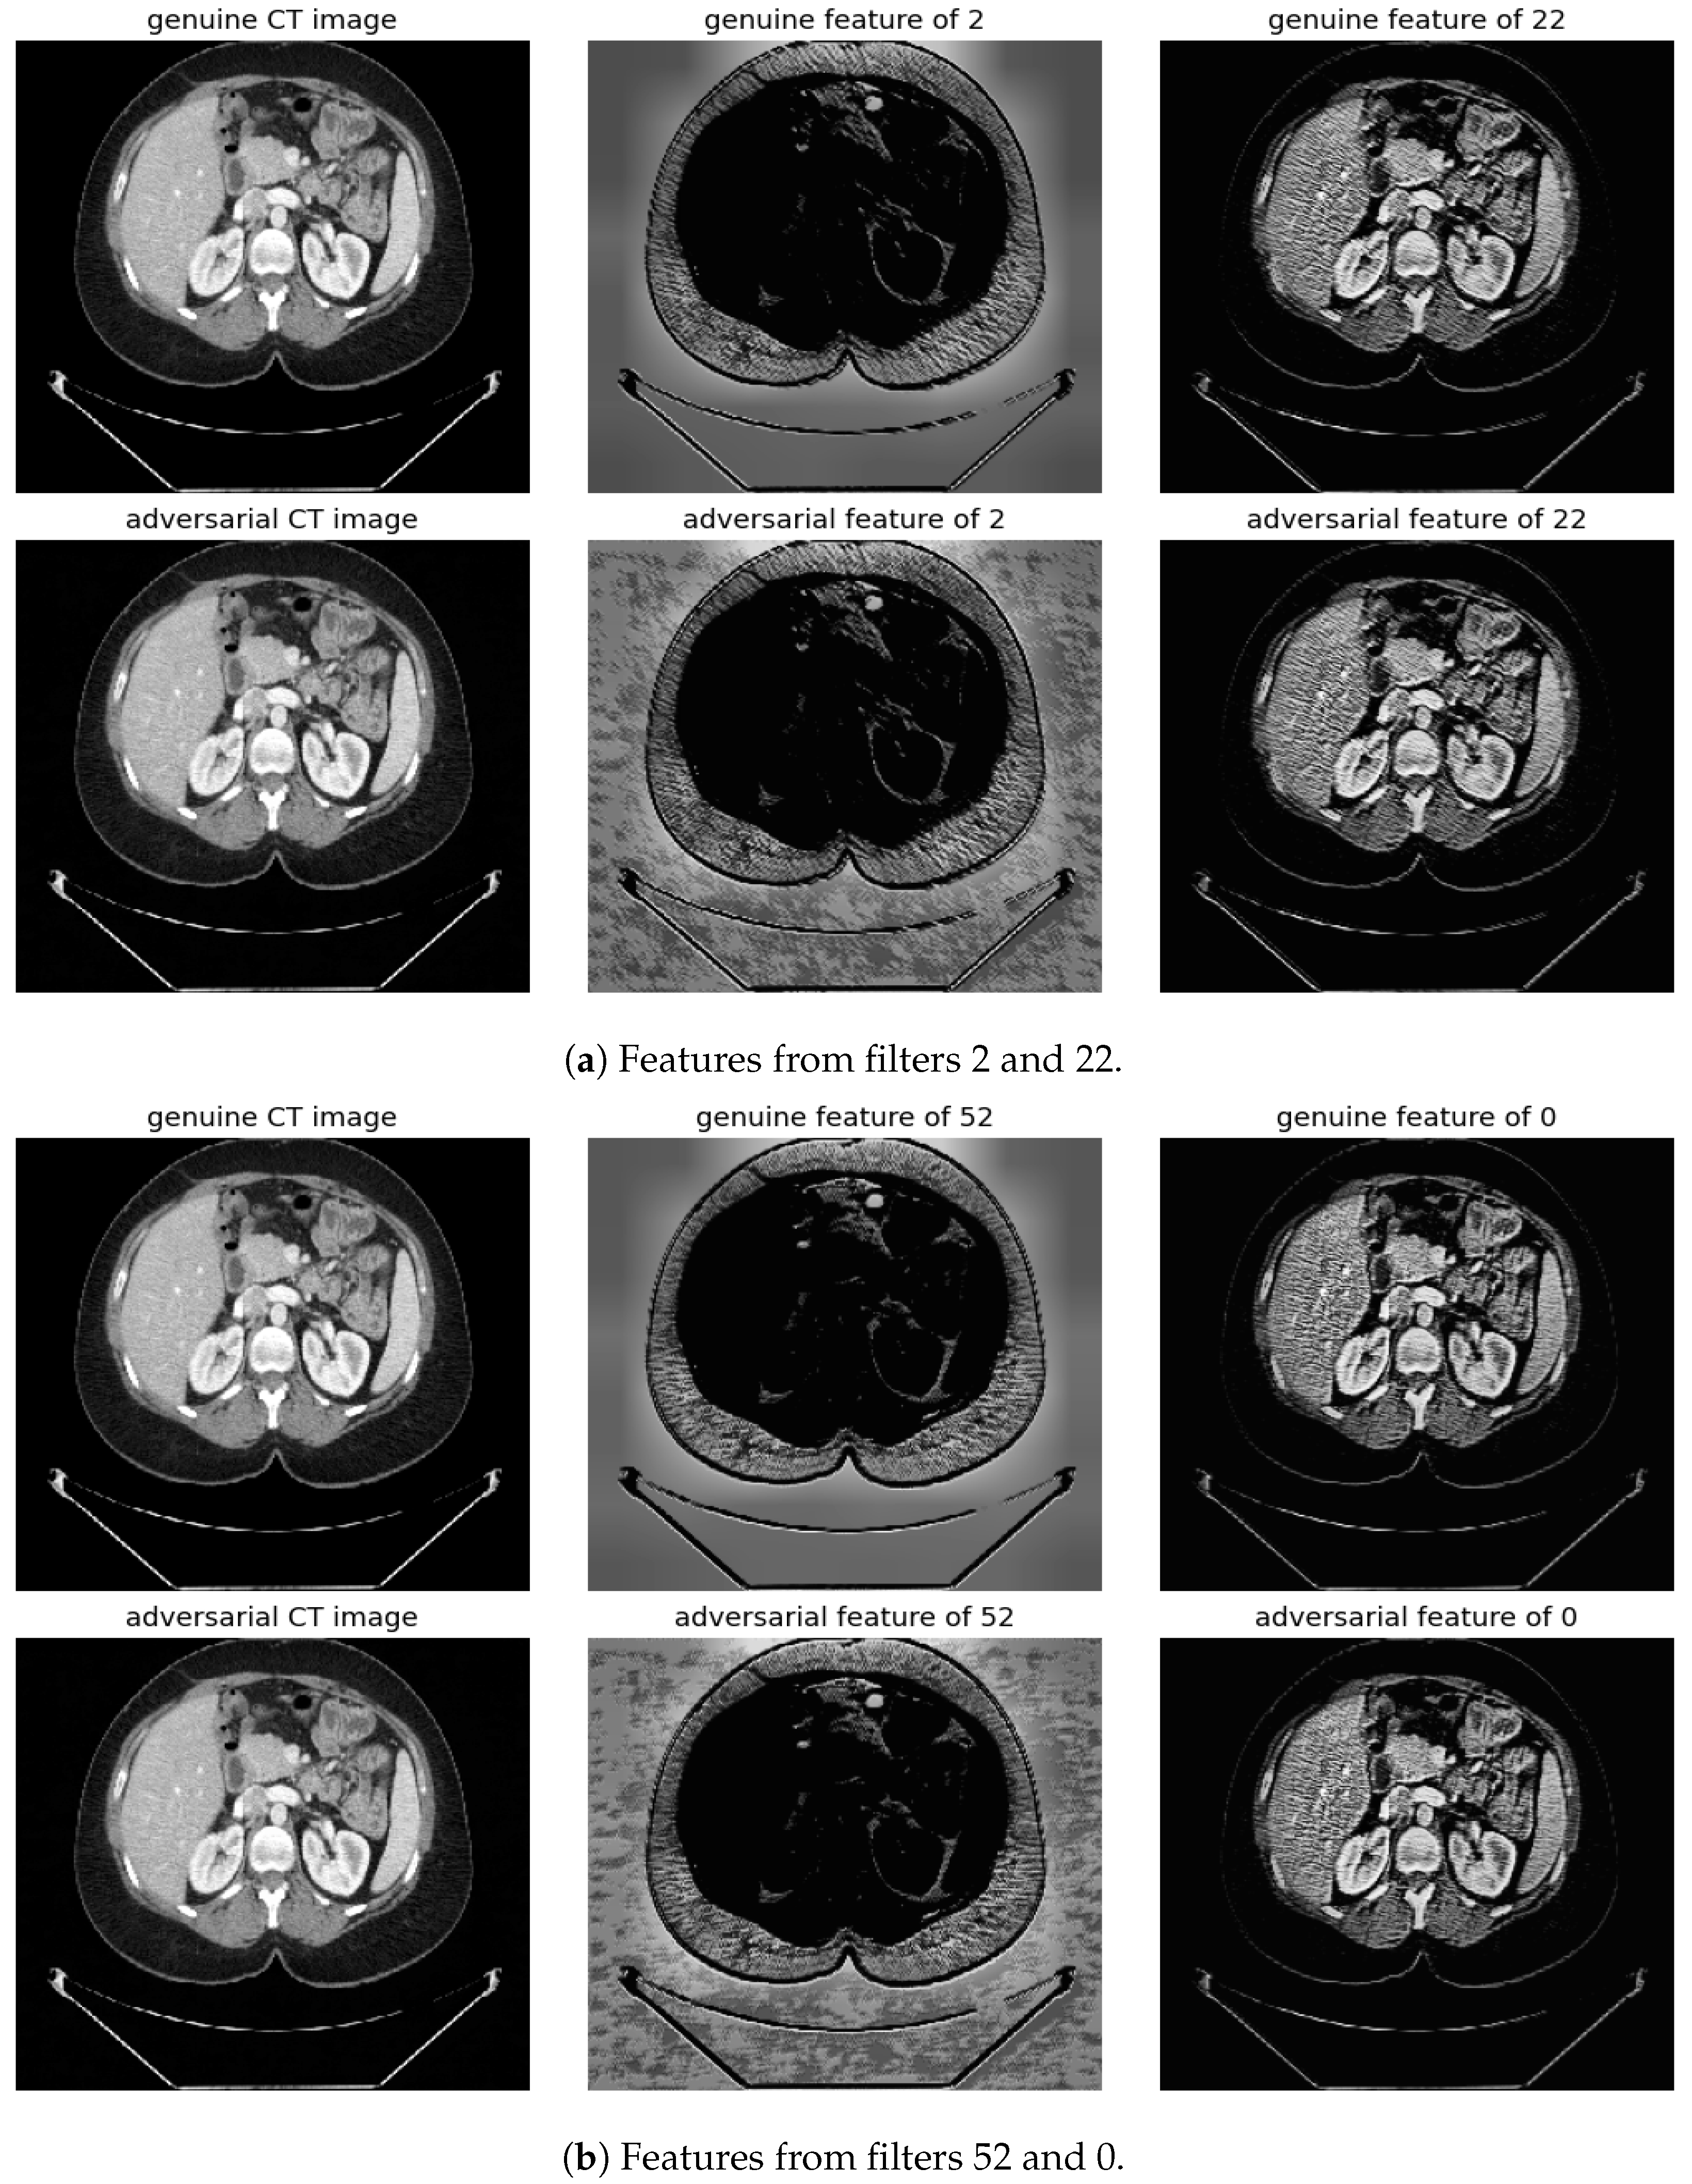

Randomly selected genuine CT samples, alongside their adversarial versions, are displayed in Figure 9, Figure 10 and Figure 11. The adversarial samples were generated using FGSM, BIM, and SMIA attack methods, each with an epsilon of 0.01. While BIM and SMIA used 5 iterations, FGSM did not. These samples represent the most challenging scenarios for human visual detection. Despite the modest epsilon value, as indicated in Table 3, the adversarial attacks have a subtle but pronounced effect. Such slight modifications can lead to major diagnostic inaccuracies potentially impacting patient care.

Figure 10.

Visualization under BIM Attack: Comparisons of features from the first layer between genuine and adversarial samples for the most sensitive (filters 2 and 52) and least sensitive (filters 22 and 0) filters.

To address this, histogram equalization as feature post-processing is applied. The visual representations underscore that while genuine and adversarial samples might appear similar to the naked eye, post-processing brings forth distinct feature differences when employing the most sensitive filters from 2 and 52. Perturbations, especially noticeable in the background of the adversarial samples, are frequently highlighted by these filters. Conversely, features processed with filters from 22 and 0, deemed less sensitive in prior analyses, fail to offer a stark visual contrast.